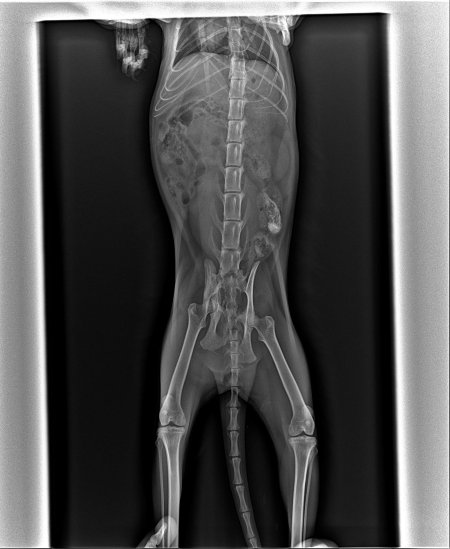

Рентгеновский эффект создает фантастические композиции в этих фотографиях девушки, чье тело становится прозрачным, демонстрируя скелет и внутренние органы. Она позирует в разных позах, ее силуэт светится загадочным свечением. Каждый кадр передает атмосферу научной фантастики и медицинского искусства. Ее кожа кажется полупрозрачной, позволяя увидеть кости и мышцы. Фотографии рассказывают о хрупкости человеческого тела и его внутренней красоте. Девушка то стоит в задумчивости, то делает грациозное движение. Эти иллюстрации вдохновляют на размышления о человеческой анатомии и уязвимости. Каждая картинка - это момент прозрения, когда внешнее уступает место внутреннему. Девушка воплощает образ современной Медузы, сочетающей красоту и загадочность.